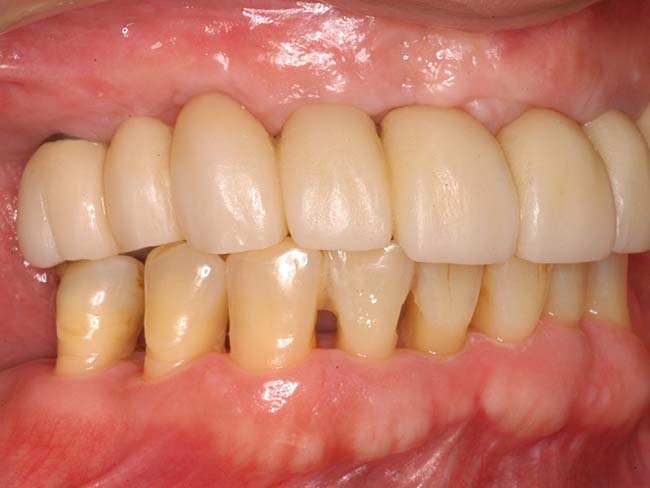

若い歯周病患者(30代)のAll-on-4

| 患者さま情報 | 治療期間 | 治療費 |

|---|---|---|

| 30代 男性 | 1年4ヶ月 | 2,491,000円 |

リスクや副作用

・保険外で高い

・治療が適応とならないケースがある。

・十分なメンテナンスがないと、失敗やトラブルを招く可能性がある。

治療経験・技術がある医師による治療が必要となる。

・外科的治療が必要